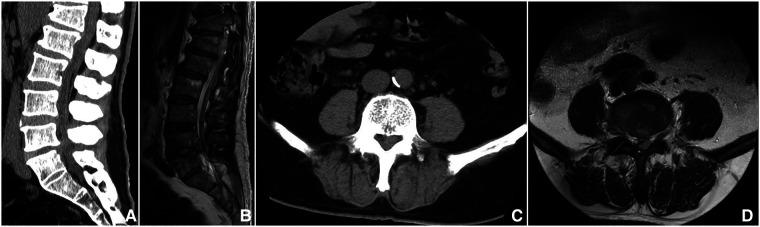

This study aims to investigate the effectiveness and feasibility of biportal endoscopic decompression, debridement, and interbody fusion, combined with percutaneous screw fixation for lumbar brucellosis spondylitis (LBS).

The data of 13 patients with LBS were retrospectively analyzed, who underwent biportal endoscopic decompression, debridement, and interbody fusion, combined with percutaneous screw fixation from May 2020 to June 2022. The patients' clinical data, the duration of operation, the estimated blood loss (including postoperative drainage), and complications were recorded. Clinical outcomes include serum agglutination test (SAT) measures Brucella antibody titer, erythrocyte sedimentation rate (ESR), C-reactive protein (CRP), the visual analog scale (VAS) scores of low back and leg, Japanese Orthopaedic Association (JOA) score, Oswestry Disability Index (ODI), American Spinal Injury Association neurological classification, and lordotic angle were analyzed. All patients were assessed using the modified Macnab criteria at the final follow-up. The intervertebral bone graft fusion was assessed using the Bridwell grading criteria.

The mean operation duration was 177.31 ± 19.54 min, and the estimated blood loss was 176.15 ± 43.79 ml (including postoperative drainage was 41.15 ± 10.44 ml). The mean follow-up period was 13.92 ± 1.5 months. SAT showed that the antibody titers of 13 patients were normal 3 months after the operation and at the final follow-up. ESR and CRP levels returned to normal by the end of the 3-month follow-up. VAS scores of low back and leg, JOA score, and ODI significantly improved after the operation throughout the follow-up period ( < 0.05). Based on the modified Macnab criteria, 92.3% showed excellent to good outcomes. One patient had only a percutaneous screw internal fixation on the decompression side due to severe osteoporosis. One case suffered a superficial incision infection postoperatively that healed with dressing change and effective antibiotic treatment. Bony fusion was obtained in all patients at the last follow-up, including 12 cases with grade I and 1 case with grade II, with a fusion rate of 92.31%.

Biportal endoscopic decompression, debridement, and interbody fusion, combined with percutaneous screw fixation is an effective, safe, and viable surgical procedure for the treatment of LBS.